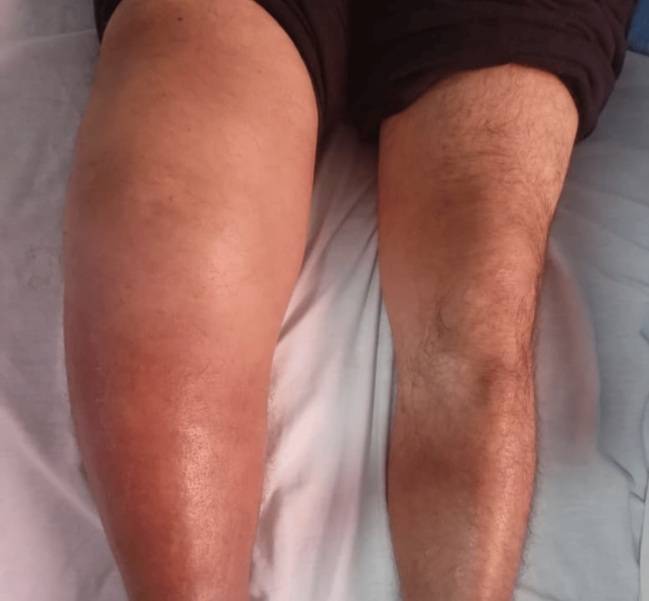

성병의 일종인 매독 후유증으로 다리 한쪽이 퉁퉁 부어오른 60대 남성의 사례가 저널에 소개됐다.

의료진에 따르면 이 62세 남성은 9개월에 결처 오른쪽 무릎에 염증이 지속된다며 병원을 찾았다. 검사 결과, 오른쪽 무릎 모양이 변형돼 있었고, 붓고, 열감이 있는 상태였지만 환자는 통증을 거의 느끼지 않고 있었다. 염증은 관절 주변 조직까지 퍼져 있는 심각한 상황이었다. 반대쪽 무릎은 정상이었다. 근골격계 초음파 사진을 찍어보니, 대량의 관절액(관절 안에 들어 있는 윤활액)이 염증 때문에 밖으로 새어 나와 있었다.

남성 역시 척수매독으로 인해 무릎 관절이 둔해졌고, 이로 인한 관절염이 생긴 것으로 의료진은 추정했다.